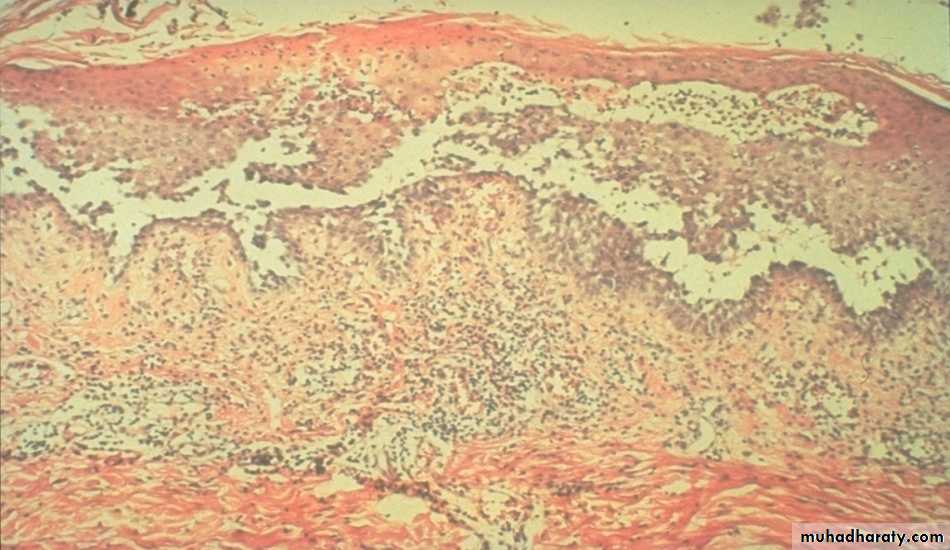

Suprabasal acantholysis results in an intraepidermal blister containing rounded keratinocytes that are separating from their neighbors. Initially, a single row of basal cells is present on the floor of the blister with dermal papillomatosis (tombstone effect). Follicular involvement by acantholysis is also common.

Skin Biopsy

Take an intact early blister from the skin or oral mm and stain it with H-E stain.

Suprabasal acantholysis and intraepidermal bullae containing large round acantholytic cells and some polymorphs & eosinophils

P. foliaceus: Subcorneal Acantholysis

P. vulgaris: Suprabasilar Acantholysis